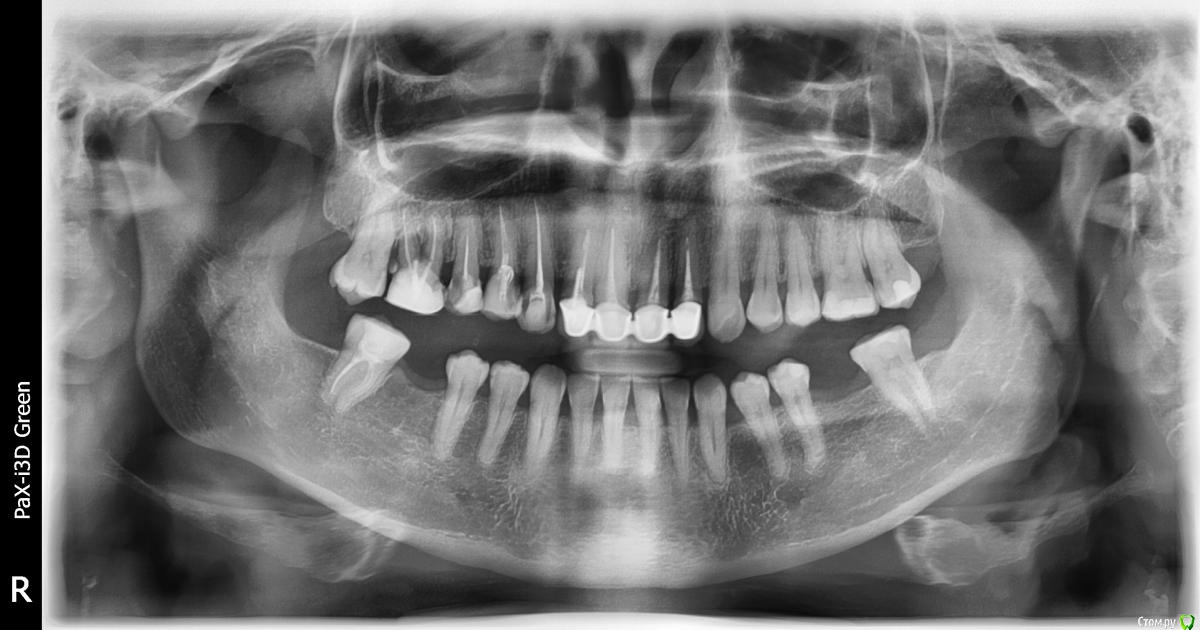

big Опубликовано 20 февраля, 2016 Поделиться Опубликовано 20 февраля, 2016 Добрый день, уважаемые специалисты. Буду признательна, если выскажете свое мнение по предложенным в двух разных клиниках вариантам протезирования. Спасибо. 1. 16 - удаление, имплант. 15, 14, 13 - отдельные коронки. Далее замена стоящего моста на отдельные коронки, по причине того, что с мостом хуже гигиена, а десны проблемные. 2. 17, 16, 15, 14, 13 - мост. 16, возможно, под удаление. И дополнительный вопрос - в первой клинике, куда обращалась к пародонтолгу, говорят, что пародонтоза нет, и жалобы на десны лишь по причине воспалительных процессов в зубах, которые снимутся новыми коронками. Ссылка на комментарий

red_butler Опубликовано 23 февраля, 2016 Поделиться Опубликовано 23 февраля, 2016 Мы видели только ОПГ, а консультировавший Вас врач и ситуацию в полости рта, если судить только по снимку, то вариант одномоментной имплантации, в вашем случае имеет право на жизнь 1 Ссылка на комментарий